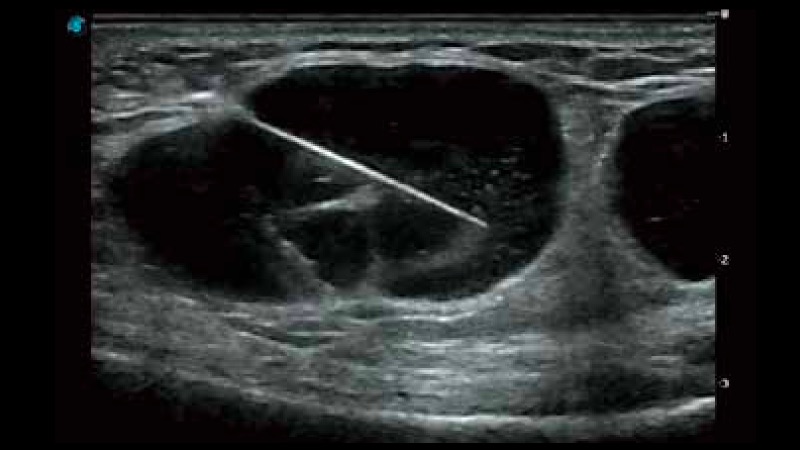

凭借狗万官方网站先进的成像技术和优异的探头技术提供的清晰的图像表现,您可以更自信地做出临床决策。